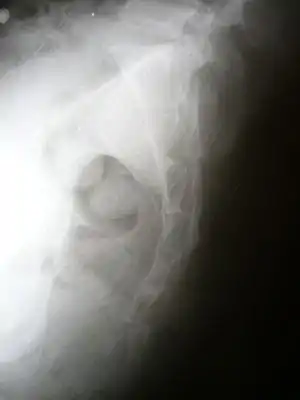

| Lateral radiograph showing a fracture of the coccyx, as well as a lower lumbar fracture | |